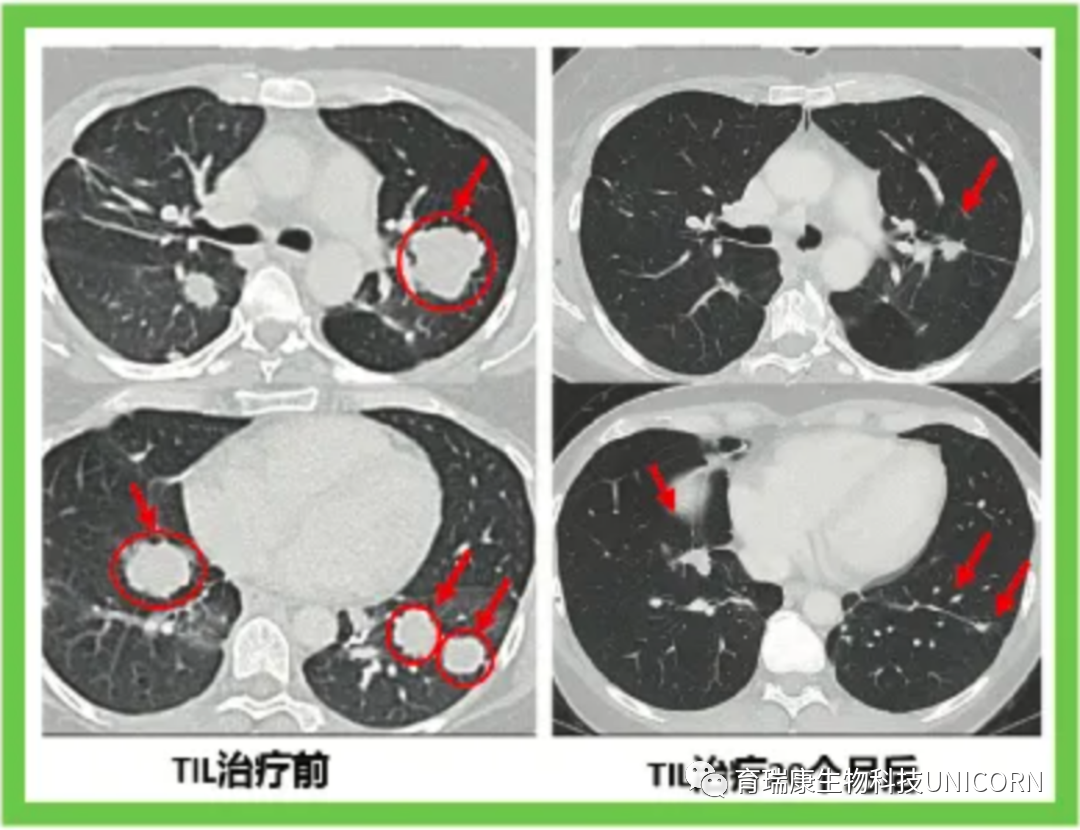

下面的对照图可以非常明显看到治疗前肺部布满的肿瘤,包括一些个头非常大的,第二次TIL治疗20个月后,这些肿瘤都非常显著地缩小了。

图片